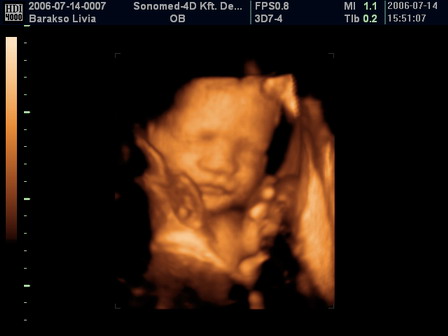

...és még valami... Ő a kisfiam :) Kép

Persze most is van gond, de megpróbálunk változtatni az egyébként szörnyen negatív hozzállásunkon... Képzeljétek észre sem vettük, milyen gyönyörű, mert úgy megijjedtünk. Azt mondta az uh-s nő, hogy az egyik agykamrát figyelni kell, mert egy picit nagyobb, mint amilyennek lennie kellene... Ez vízfejűségre utal, de most várnunk kell... :cry:

Nagyon gyönyörű gyermek! :D :D :D Igazi kisember formája van!

Livi, a babád csodálatos és egészséges!!!! Olyan gyönyörű, hogy egyszerűen egészségesnek is kell lennie! Ne idegeskedj, a dokik szeretik mindenféle hülyeséggel sokkolni a szülőket, reményeim szerint alaptalanul! Simogasd meg a nevemben a pocit, és énekelj a babónak valami szép dalt!

Nagyon tetszik a fiad! Kimondottan szép arcú gyerek, és minden rendben lesz! Nincs anya akit valamivel meg nem ijesztettek a terhessége alatt! Ne aggódj, és mindenképp írd meg a kontrollt!

Nagyon szep a kisfiad a kepen :) Sajnalom, hogy ratok ijesztettek ennyire, de en is bizom a kisfiuban. Ilyenkor meg nagyon sokat fejlodnek a babak es kesz csodakra kepesek. Mikor kell ujbol menni kontrollra?

Bali, nagyon aranyos ez a kis gyerkoc :) Nagyon edes pofija van :)

Annyira szep kisfiu!!!! :D

Ha van meg kep feltehetned,ugy szeretem a 4(3?)D-s kepeket!!!

Nevet tudjatok mar????

En is nagyon-nagyon szoritok hogy ez csak egy rossz diagnozis legyen!!!!!!!!!